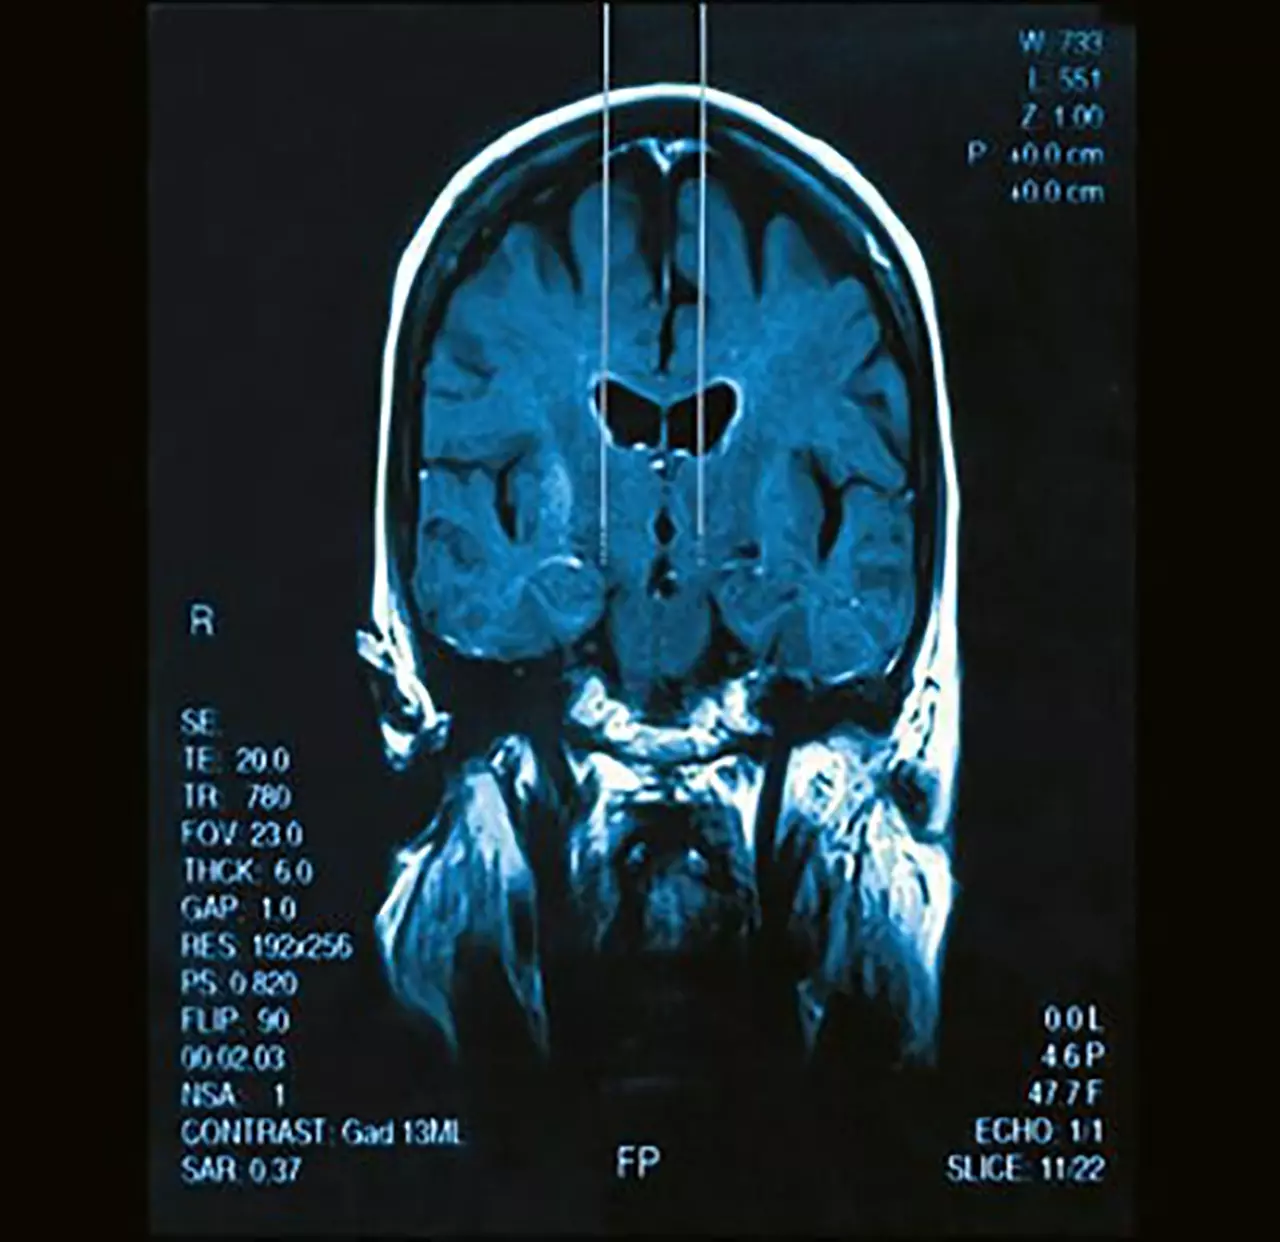

โรคพาร์กินสัน เป็นโรคสมองเสื่อมแบบหนึ่งจะเรียกว่าเป็นโรคพี่ โรคน้องกับอัลไซเมอร์ก็ว่าได้ ถึงแม้ว่าอาการจะไม่เหมือนกัน โดยที่ในโรคพาร์กินสันนั้น เป็นเรื่องของการเคลื่อนไหวฝืด แข็ง จะมีสั่นมากหรือสั่นน้อยก็ได้